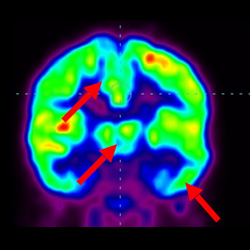

干細胞治療腦癱后改善的客觀放射學證據

細胞治療前 PET CT 掃描顯示神經組織中的藍/黑色區域,表明腦癱引起的大腦損傷。

細胞治療后,藍色和黑色區域減少,并且看到更活躍的區域。這表明損傷減少并改善了大腦功能。

這證明細胞療法是治療腦癱兒童安全有效的方法。細胞療法可以更新大腦損傷的核心,并且可以通過 PET CT 掃描來監測大腦的改善情況。這些細胞療法與標準治療一起促進腦癱兒童的生長和改善。